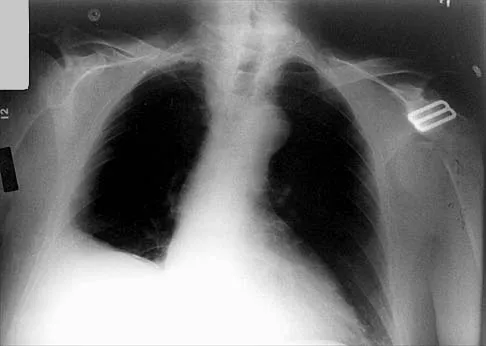

Which of the following findings is seen in the chest radiograph shown in Figure 13?

Explanation